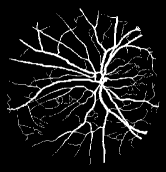

Refer to caption

Figure 1: Vessel segmentation results of side-output(s-out) layers produced by three networks. From top to bottom the network is normal DSN (with no short connections), BS-DSN (DSN with bottom-top short connections) and BTS-DSN (DSN with both bottom-top and top-bottom short connections), respectively.

As pointed out in recent works [15, 17], a good semantic segmentation network should learn multi-level features. Further, it should have multiple stages with different receptive fields to learn more inherent features from different scales. FCN, taken as an example, uses skip connections to fuse multiple stages outputs, as well as the HED network, in which a series of side-output layers are added after each stage in VGGNet. The HED network was first proposed for edge detection, and further used for image-level vessel segmentation in recent studies [6, 16], with significant performance. However, our experimental results show that such network architecture is not appropriate for vessel segmentation directly. Figure 1 provides such an illustration. Reasons for this phenomenon are straightforward. On one hand, the side-output of the first layer often contains too many noises. On the other hand, the features produced by the last side-output layer are too coarse due to information loss of pooling operation. Obviously, the inaccurate vessel map of side-output1 and side-output4 should have negative impacts on the final segmentation result.

In addition, we can observe from Figure 1 that the side-output1 and side-output4 of the BTS-DSN were more accurate compared with those of the DSN.